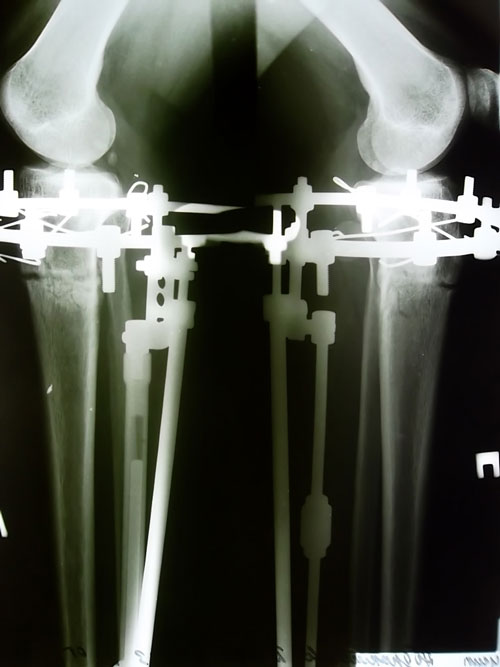

- Диагноз: о-образная деформация нижних конечностей

сегодня 78 день после ОП

что-то я не получила ответа на мой рентген-снимок ,а чемодан уже собрала

снимки я свои видела -я бы хотела оценку к ним или какие-то комментарии,я могу ехать ?

Молодец! Через 3 недели высылайте рентген, попробуйте эл. почтой. Нужно приложить рентгеновские снимки на окно (но не прямые солнечные лучи) и сфотать. Посмотрим, что получится, если что вышлите почтой. Ходите, результат у Вас не должен, а будет отличным!Наталья!